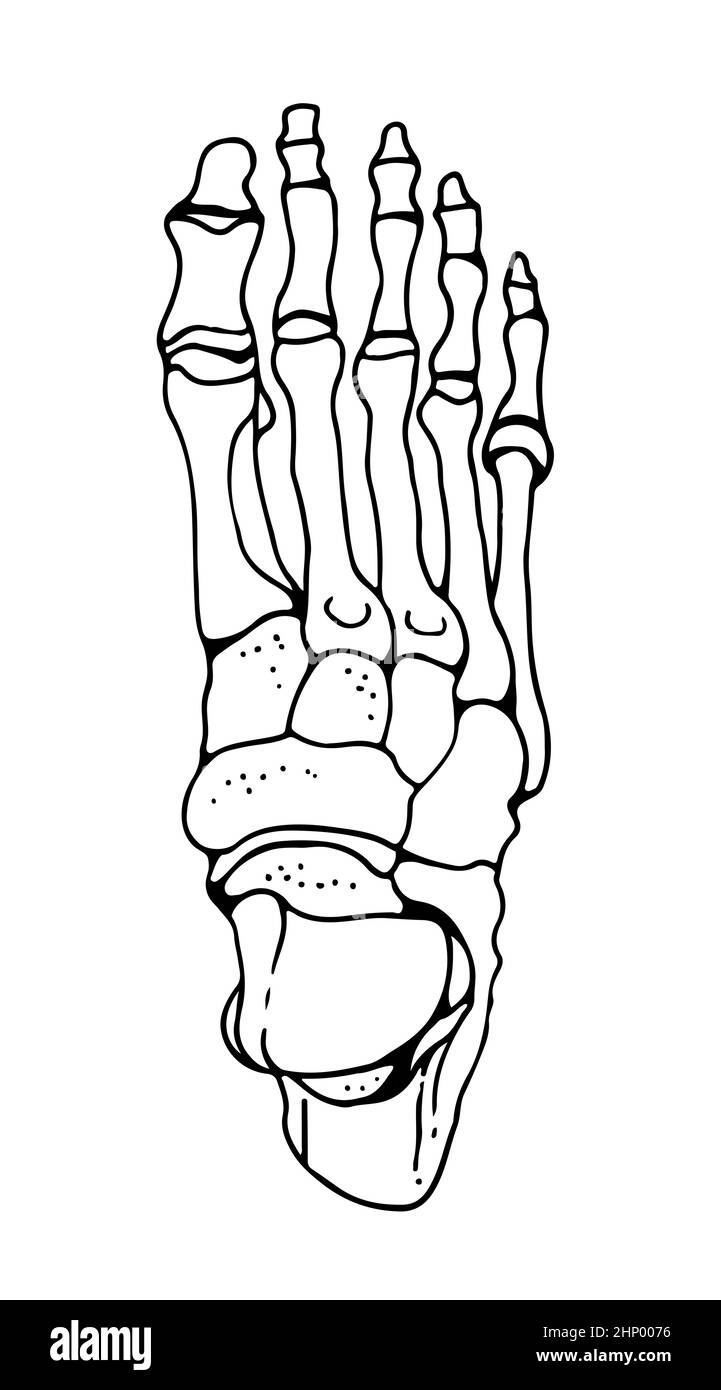

RF2HP0076–OS du pied humain, illustration vectorielle dessinée à la main isolée sur fond blanc, esquisse anatomique en médecine orthopédique

RF2HPABHW–OS du pied humain, illustration vectorielle dessinée à la main isolée sur fond blanc, esquisse anatomique en médecine orthopédique